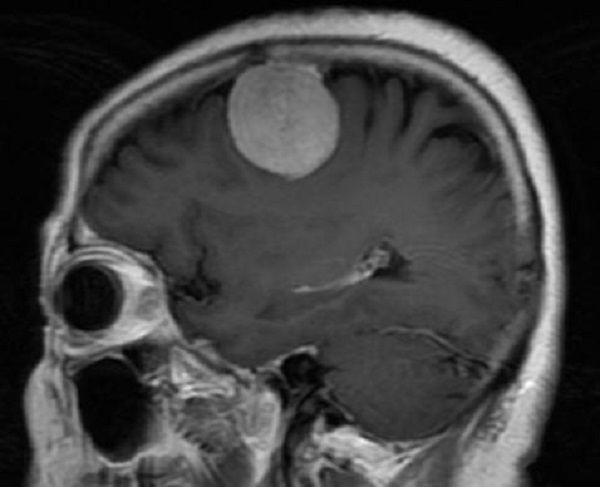

近日,二一五医院神经重症监护室谢国强主任团队成功应用3D打印导板技术,为一例患有颅内肿瘤患者规划了个体化手术方案,精确定位肿瘤部位,在显微镜下全切肿瘤。 63岁的李女士以“间断性头痛、头晕3周”主诉入院。头颅CT及MRI提示:右额叶占位病变,病灶呈均匀强化,可见脑膜尾征,考虑脑膜瘤。

神经重症监护室谢国强主任团队全方位分析患者病情,利用在医学影像数据化处理方面的技术优势,为患者制定了个体化手术方案。使用3D slicer软件重建肿瘤并在体表投影,进而使用3D打印导板技术设计并制作3D打印模型,做到肿瘤的精准定位,在显微镜下全切肿瘤,最大限度减少手术创伤。术后,在神经重症监护室护理团队的精心护理下,患者神志清楚,语言及四肢活动正常,无任何神经功能障碍。

术后CT: